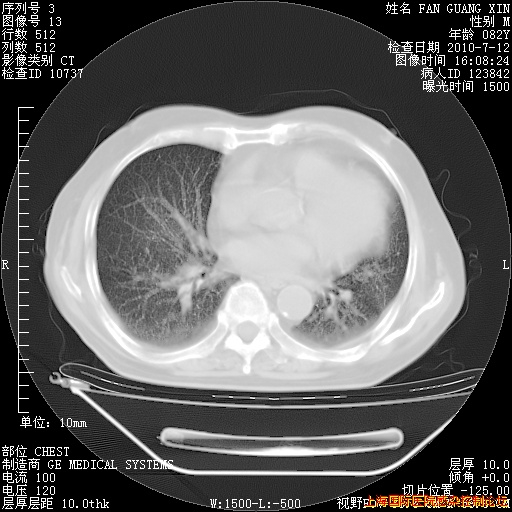

补发6月12日肺部CT肺窗

6月12日肺窗